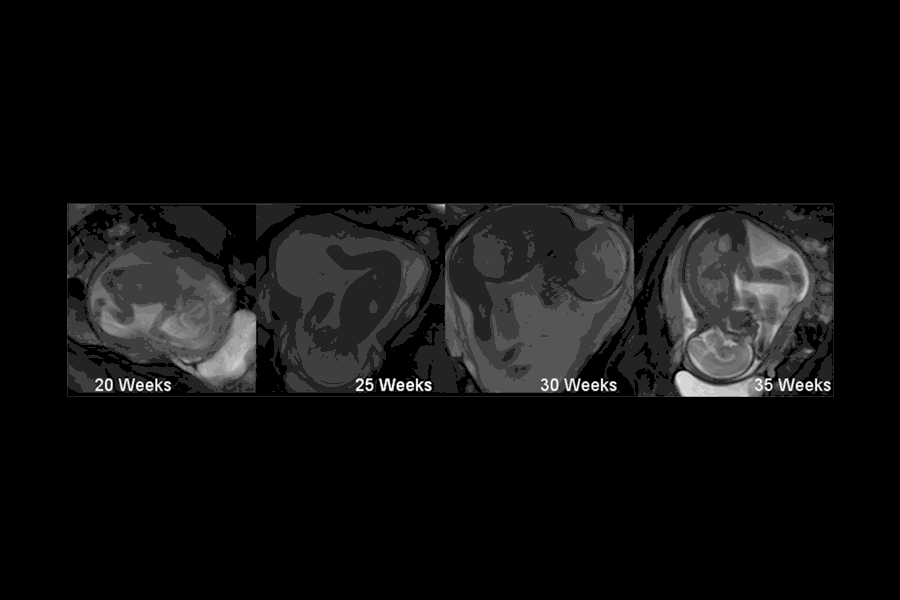

اولین باری که زن باردار متوجه لگد زدن کودک در شکمش می شود، بسیار هیجان انگیز است. متوجه می شود که مخلوق کوچکی در شکمش هست که مستقل از او عمل می کند. اما چرا بچه ها در شکم مادرانشان لگد می زنند. اگرچه فضای تنگ رحم مادر کوچکتر از آن است که ورزش کرد؛ مشخص شده است که این لگد زدن ها برای سلامت استخوان بندی کودک و رشد مفاصل حیاتی است. مطابق مقاله ای که در مجله اولتراسیوند منتشر شده است، شروع حرکت بچه ها در رحم، اوایل هفته ۷ است. زمانیکه به آرامی گردنش را خم می کند. همانطور که نوزاد رشد می کند حرکات بیشتری همانند، سکسکه کردن، حرکات دست و پا، خمیازه کشیدن و مکیدن انگشت شصت را انجام می دهد. اما مادر آنها را حس نمی کند تا هفته ۱۶ تا ۱۸ که نوزاد قوی تر شده و قادر به مشت زدن و لگد زدن است. این که حرکات در کنترل نوزاد است یا فقط یک رفلکس؛ در کالج امپریال مورد بررسی قرار گرفت و به این نتیجه رسیدند که حرکات اولیه احتمالا فقط رفلکس بوده که از ستون فقرات نشات می گیرید، ولی هنگامیکه حرکات هماهنگ تر می شوند، مغز مقدار و زمان حرکات را کنترل می کند. اگرچه بطور یقین نمی توان گفت که این حرکات ارادی است ولی قطعا این جنبش و حرکت بسیار مهم است. نوزاد برای اینکه بعد از زایمان سلامت باشد، مخصوصا سلامت استخوان ها و مفاصل ؛ به این حرکات نیاز دارد. بطوریکه فقدان این حرکات؛ منجر به اختلالات مادرزادی، همانند کوتاهی مفاصل و استخوانهای نازک می شود که به راحتی می شکنند. مادران گاهی نگران هستند که آیا نوزاد در شکم آنها حرکت و جنبش کافی را دارد؟ پاسخ به این سوال سخت است. زیرا نمی توان گفت که دقیقا چه مقدار جنبش نوزادان نیاز دارند. زیرا اصولا بررسی این امر فقط در بیمارستان امکان پذیر است و مشخص است که این امکان وجود ندارد، مادر دائم تحت کنترل باشد. ولی اخیرا مانیتوری را آزمایش کرده اند که می تواند به صورت دقیق، تنفس، حرکات ناگهانی و دیگر حرکات معمول نوزاد را در شکم تعیین کند. بعضی تحقیقات می گوید که حرکات نوزادان پسر در رحم بیشتر از دختران است و بعضی از مادران معتقدند که در بارداری دوم حرکات نوزاد را بیشتر حس کرده اند که شاید به دلیل کش آمدن بیشتر عضلات رحم در بارداری دوم، نسبت به بارداری اول باشد. احساس حرکات نوزاد در شکم شاید حس عجیبی باشد؛ اما به سادگی نشانه رشد سالم نوزاد است.